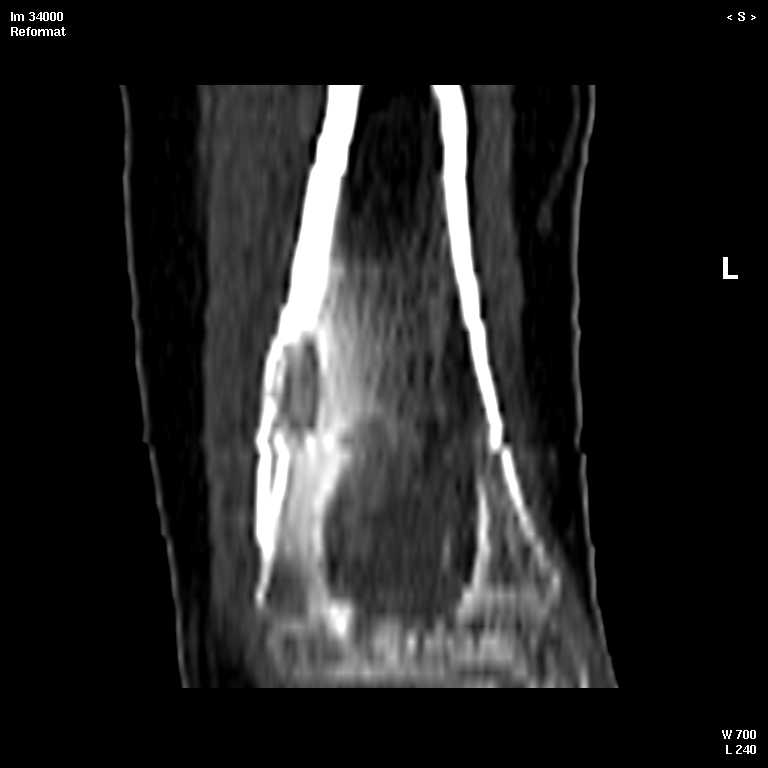

В обсуждении темы возникла необходимость дополнительных данных.

КТ изображения передаю на мой взгляд самые демонстративные. Их любезно записал коллега,

проводивший исследование в другом городе.

Прошу прощения за немного некоректную отправку КТ-снимков но по другому не получается :)